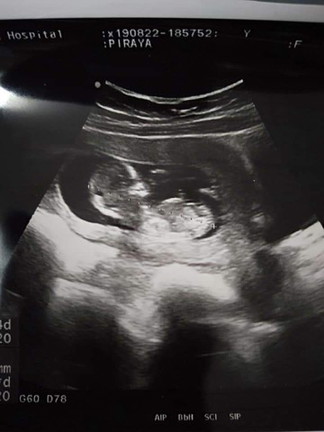

อัลตร้าซาวด์ จะได้เพศชายหรือหญิง

สรุปได้ลูกชายได้บ้านนี้ดีใจมากเลยสมใจแล้วค่ะหญิงคนชายคน